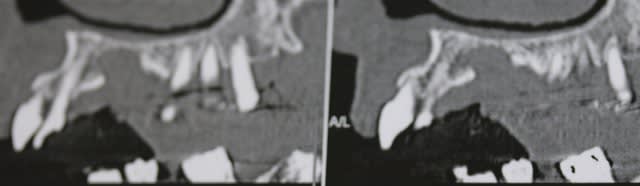

11/12/2015 à 12h29

controle du cas de la page 19 , ce jour .

faut aimer l'aspect champignon , mais ça va , chance !!!!

11.12 - Eugenol

oui ca avance... enfin.....tu aurais dû sous-exposer la rx encore un chouia et là on aurait dit que c'est carémment cicatrisé.

voilà ,j'ai repris la photo de la meme radio , ce qui ne change pas le fait qu'elle soit tjs sur l'arcade :-)